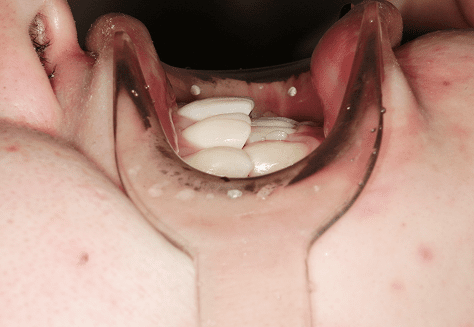

S.K

治療前

治療後

主訴

歯が重なっていて気になる。前歯が出ていて唇が閉じにくい。ハミガキがしにくい。

診断

上顎前突・叢生

年齢/性別

20代/男性

抜歯部位

上下第三大臼歯

使用装置

上下インビザライン

保定装置

上下ビベラリテーナー

料金

初回資料採得・・・・・・・30,000円

診断料・・・・・・・・・・33,000円

動的治療終了時資料採得・・5,500円 -

基本料金

990,000円

診察料金

1,100円×33回

治療期間

3年5カ月